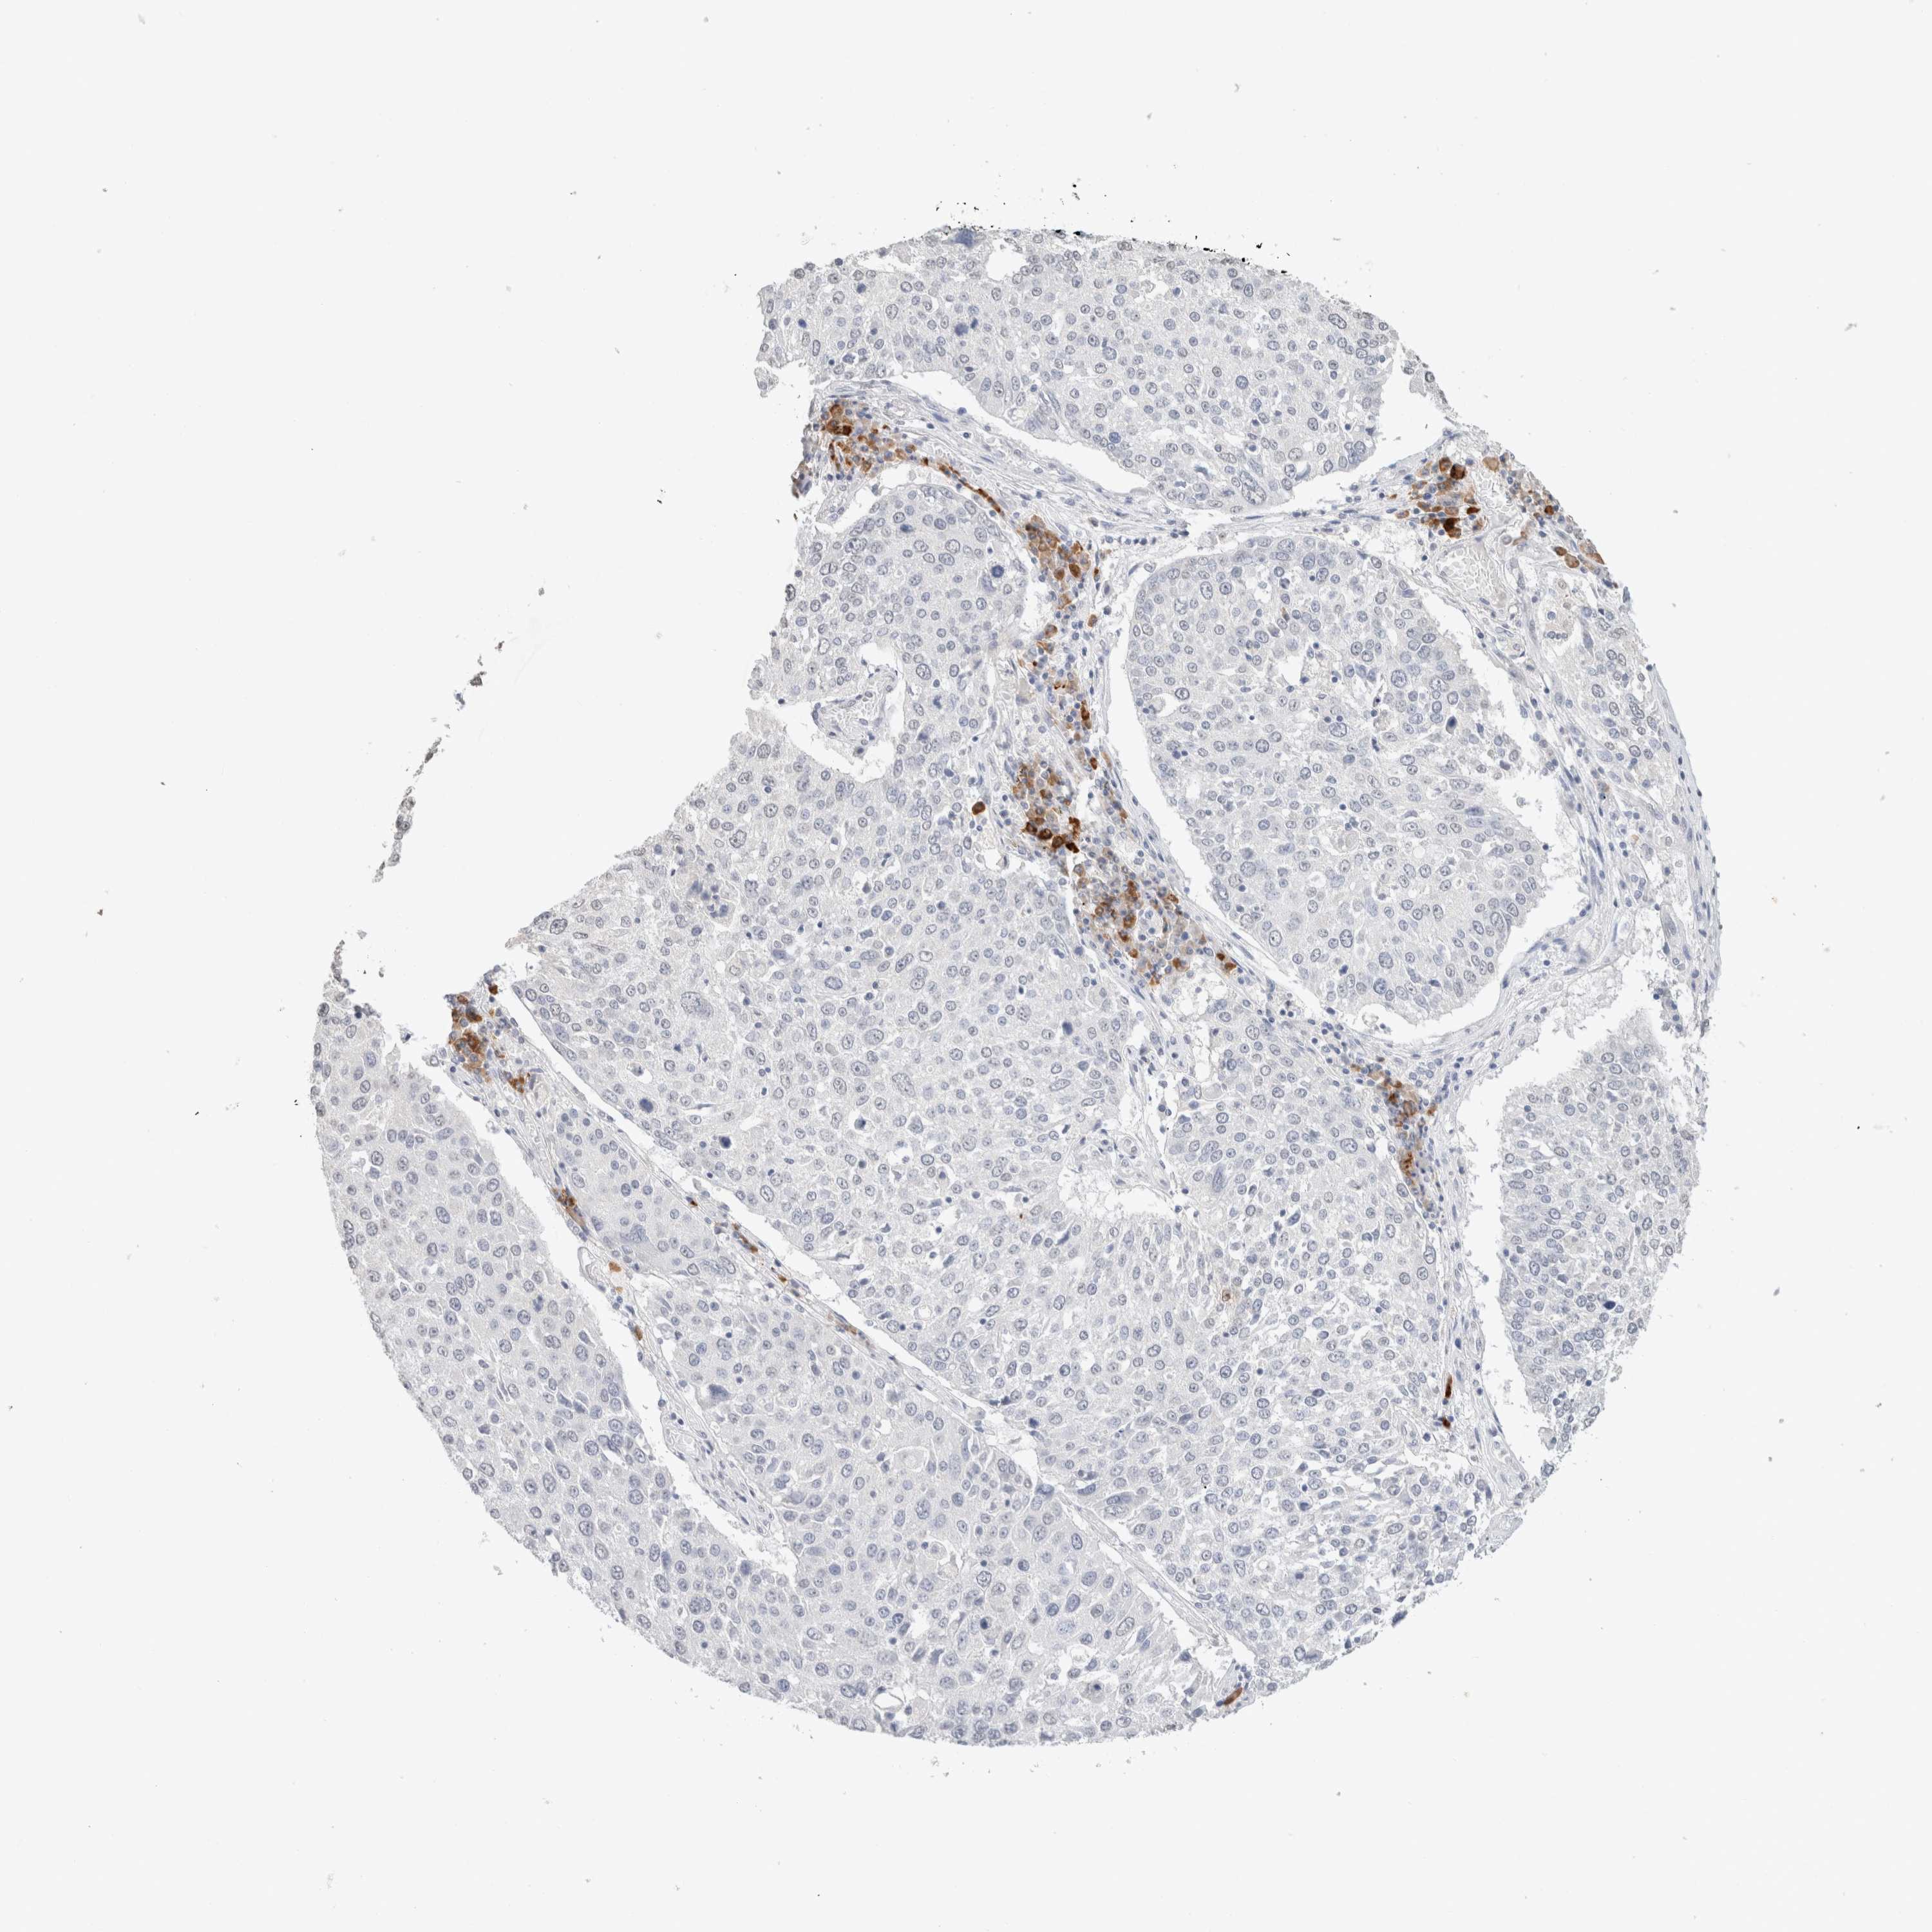

LUNG SQUAMOUS CELL CARCINOMA (TCGA) - Interactive survival scatter ploti

The Survival Scatter plot shows the clinical status (i.e. dead or alive) for all individuals in the patient cohort, based on the same data that underlies the corresponding Kaplan-Meier plots. Patients that are alive at last time for follow-up are shown in blue and patients who have died during the study are shown in red.

The x-axis shows the expression levels (FPKM) of the investigated gene in the tumor tissue at the time of diagnosis. The y-axis shows the follow-up time after diagnosis (years). Both axes are complimented with kernel density curves demonstrating the data density over the axes. The top density plot shows the expression levels (FPKM) distribution among dead (red) and alive patients (blue). The right density plot shows the data density of the survived years of dead patients with high and low expression levels respectively, stratified using the cutoff indicated by the vertical dashed line through the Survival Scatter plot. This cutoff is automatically defined based on the FPKM cutoff that minimizes the p-score. The cutoff can be changed by dragging the vertical line or by entering a cutoff value in the square labeled "Current cut-off".

Under the Survival Scatter plot the p-score landscape (black curve; left axis) is shown together with dead median separation (red curve; right axis). Dead median separation is the difference in median mRNA expression between patients who have died with high and low expression, respectively. It is calculated as follows: median FPKM expression of dead patients with high expression - median FPKM expression of dead patients with low expression. This is intended to aid the user in visually exploring custom cutoffs and the associated p-scores and dead median separation.

Individual patient data is displayed and can be filtered by clicking on one or more of the category buttons on the top of the page. Categories describing expression level and patient information include: high, low, alive, dead, female, male and tumor stages. The scale of the x-axis can be toggled between linear and log-scale by clicking on the "x log" button. Mouse-over function shows TCGA ID, patient information and mRNA expression (FPKM) for each patient.

& Survival analysisi

Kaplan-Meier plots summarize results from analysis of correlation between mRNA expression level and patient survival. Patients were divided based on level of expression into one of the two groups "low" (under cut off) or "high" (over cut off). X-axis shows time for survival (years) and y-axis shows the probability of survival, where 1.0 corresponds to 100 percent.

CD80 is not prognostic in Lung Squamous Cell Carcinoma (TCGA)

: 0.59

Average pTPM 1.2

Number of samples 489